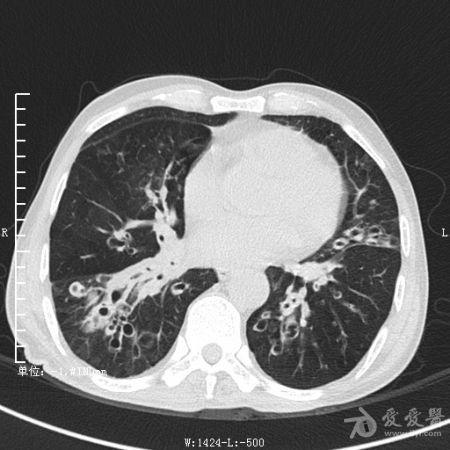

典型支气管扩张及肺水肿CT片

典型支气管扩张肺水肿